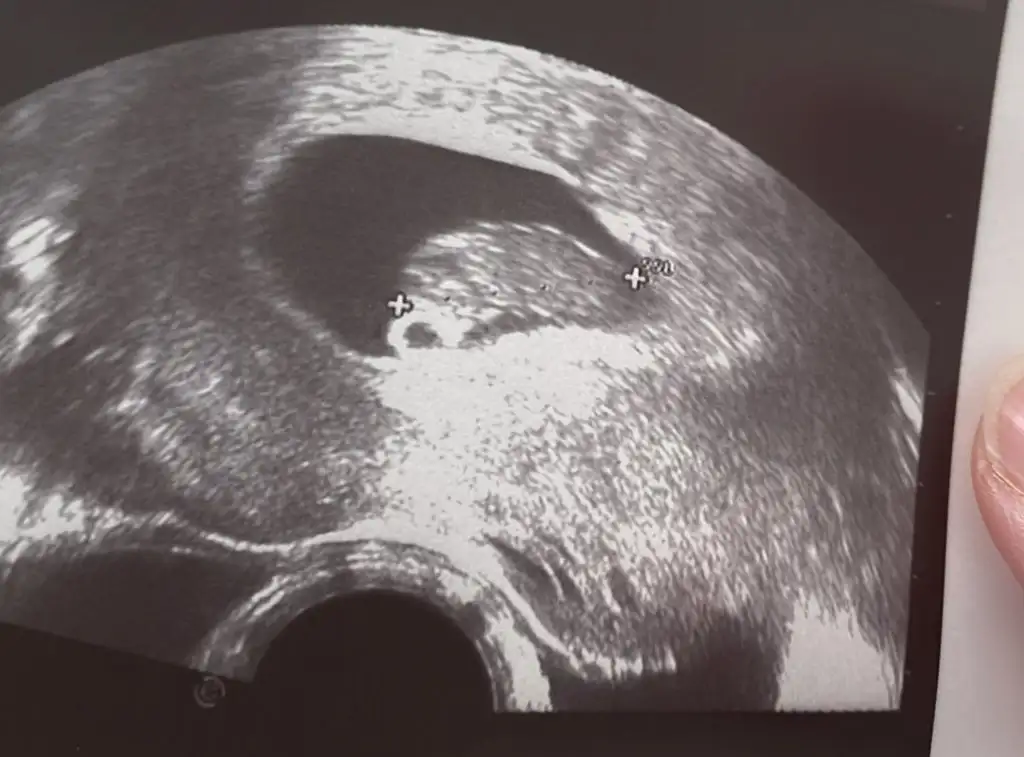

12 +3 ultrason görütüsü tahmininizi merk ediyorumSelam Kızlarbir çok kişi gruplardan beni bilir. Yine yetiştim imdatlara

5 ve 14. haftaya kadar olan ultrason fotolarınızı paylaşın. Vajinadan mı yoksa karından mı çekildiğini ve kaç haftalık olduğunu da mutlaka belirtin.